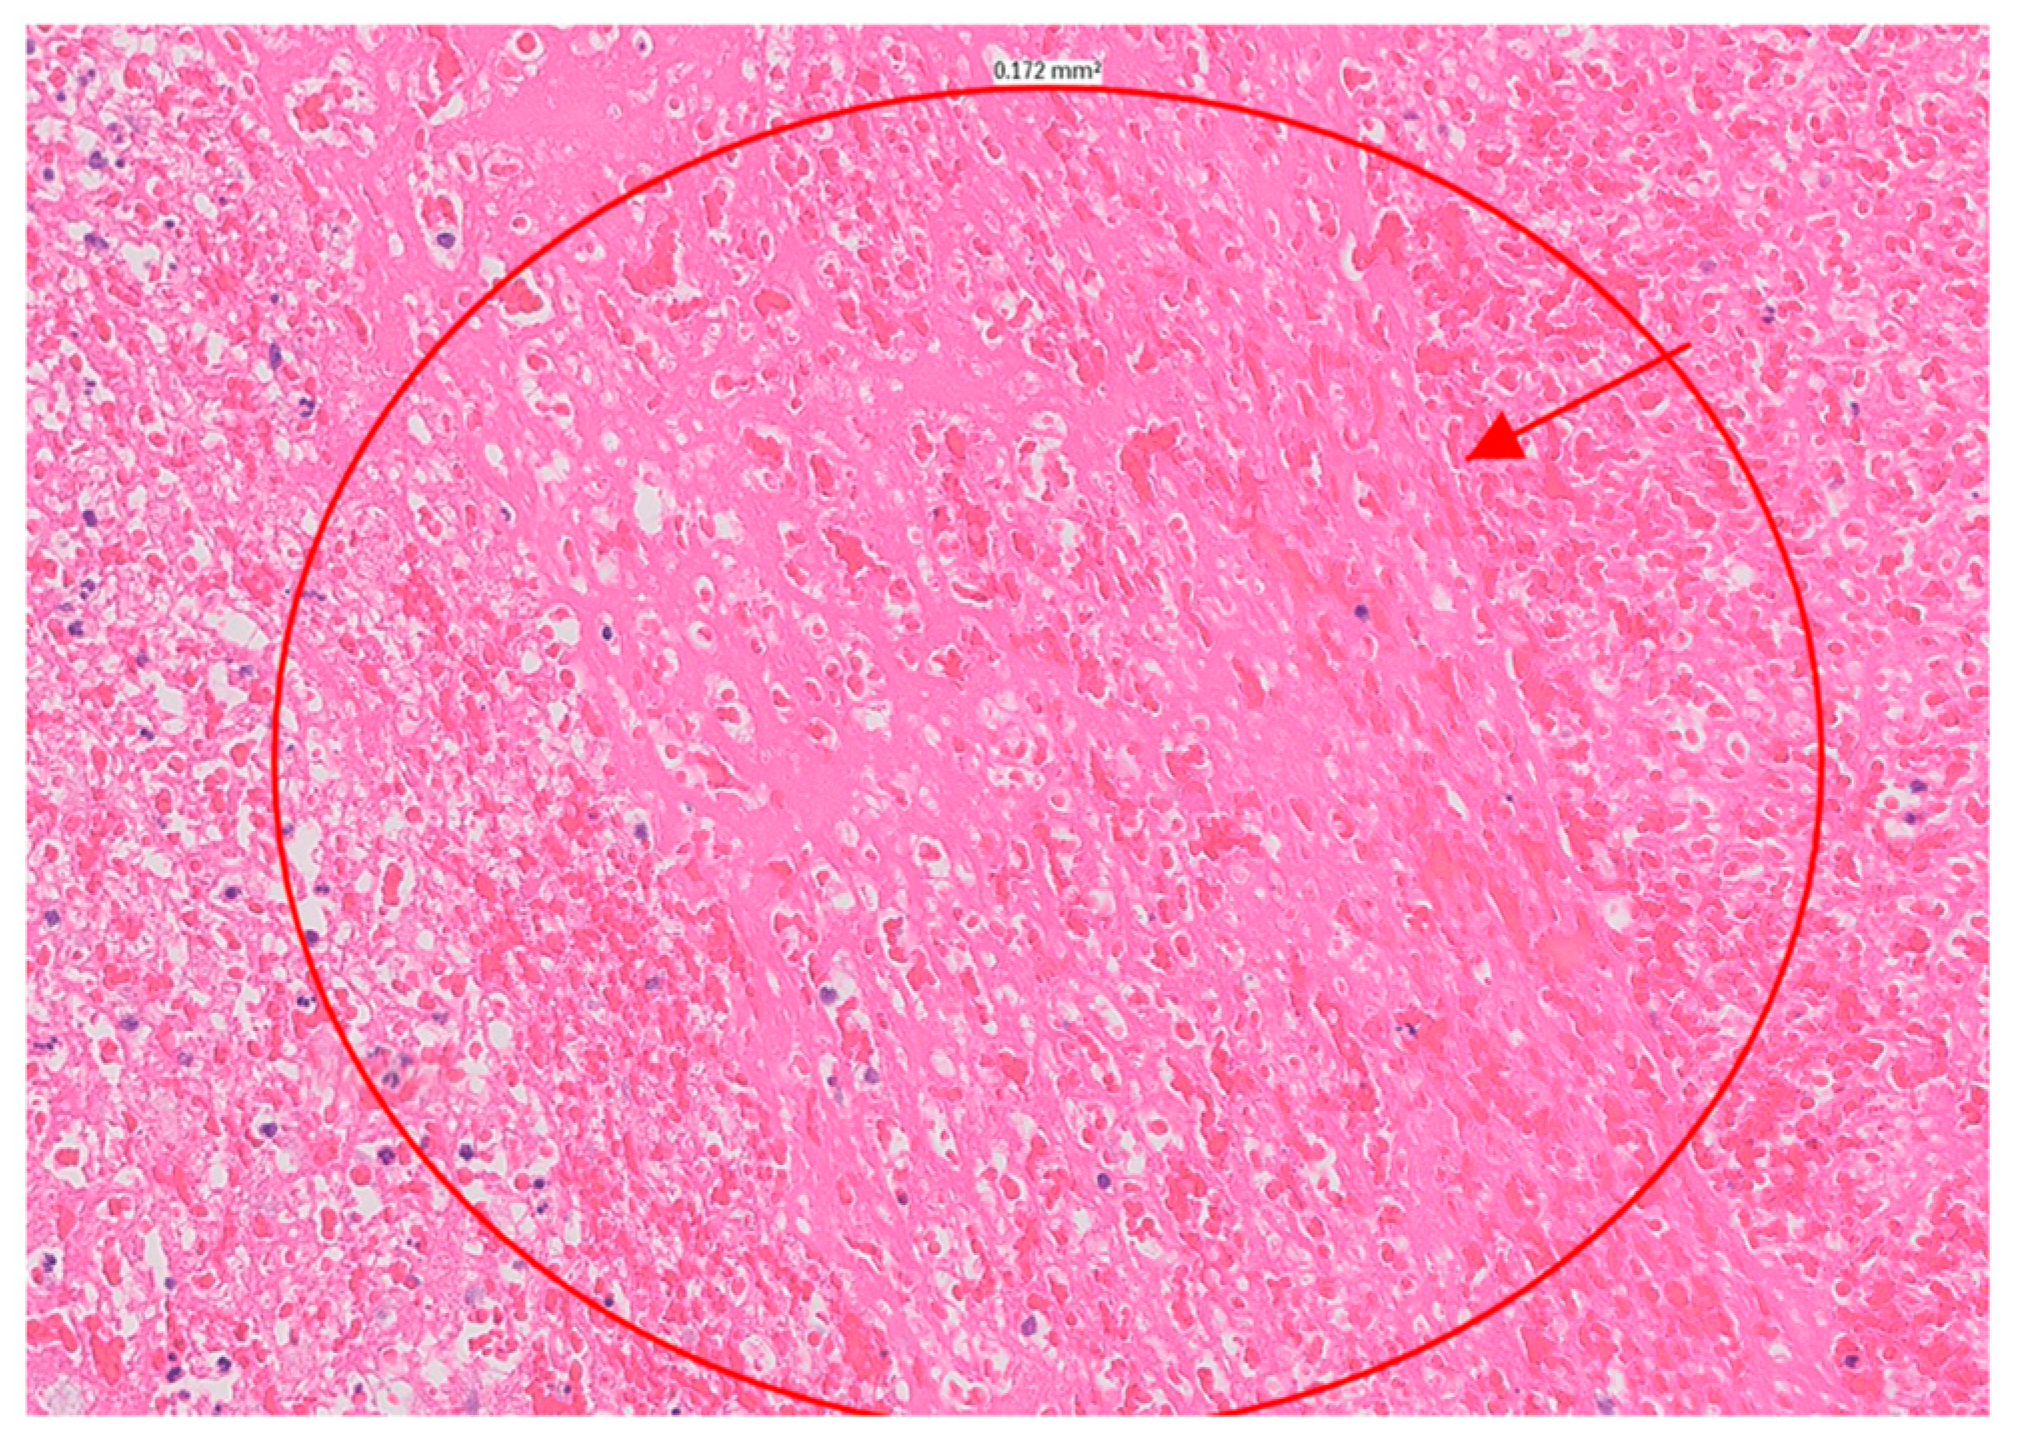

At this point in the patient’s course, the likelihood of infectious endocarditis was considered significant. Blood cultures and serologic markers were drawn, and broad-spectrum antibiotics were initiated. Due to the severity of the MR, which was accompanied by acute heart failure, the patient was referred for urgent surgical intervention and underwent mitral valve replacement within 24 h of her admission. During surgery, two large masses of tissue attached to the posterior annulus of the mitral valve were noticed. The masses appeared to be blocking the valve opening and infiltrating the posterior leaflet, posterior annulus, and surrounding cardiac tissue. The cardiac surgeon noted that the left atrial wall was infiltrated, suggesting a tumor. However, the pathologic evaluation revealed a large, organized thrombus, with no evidence of malignancy (

Figure 3). Blood cultures, as well as serological tests for Coxiella burnetii and Bartonella henselae, were negative, as was a pan-bacterial PCR of the surgical sample. Serological tests for antiphospholipid autoantibodies (aPL) were negative, including anticardiolipin antibodies, anti-β2 glycoprotein-1 antibodies as well as a LAC test. Antinuclear antibodies were positive at a titer of 1/640, with a homogeneous and speckled pattern. Anti-dsDNA antibodies were positive at a titer of 1/160, while C3 and C4 were within the normal range.

The patient was diagnosed with marantic (Libman–Sacks endocarditis (LSE)) endocarditis. LSE is a form of nonbacterial thrombotic endocarditis often associated with SLE. It is characterized by the presence of sterile vegetations on the heart valves, which can lead to embolic events and other complications. Given this diagnosis, antibiotics were discontinued [